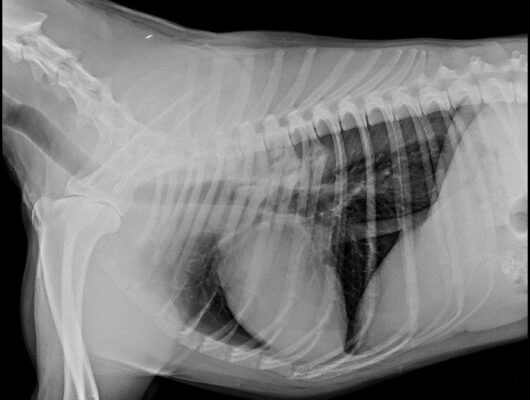

Its about a dog, 1,5 years old, intact, Tervuerense Herder X Groenedaeler which has since one month ago according with the owner, gagging symptoms. The owner mentioned that sometimes the dog coughs and then he vomit some white <<foam>> . The dog eats barf…

The radiologist mentioned also that there is a suspicion of an old trauma but because the <<instellings>> of the xrays might not be the best, it might be also an artifact.